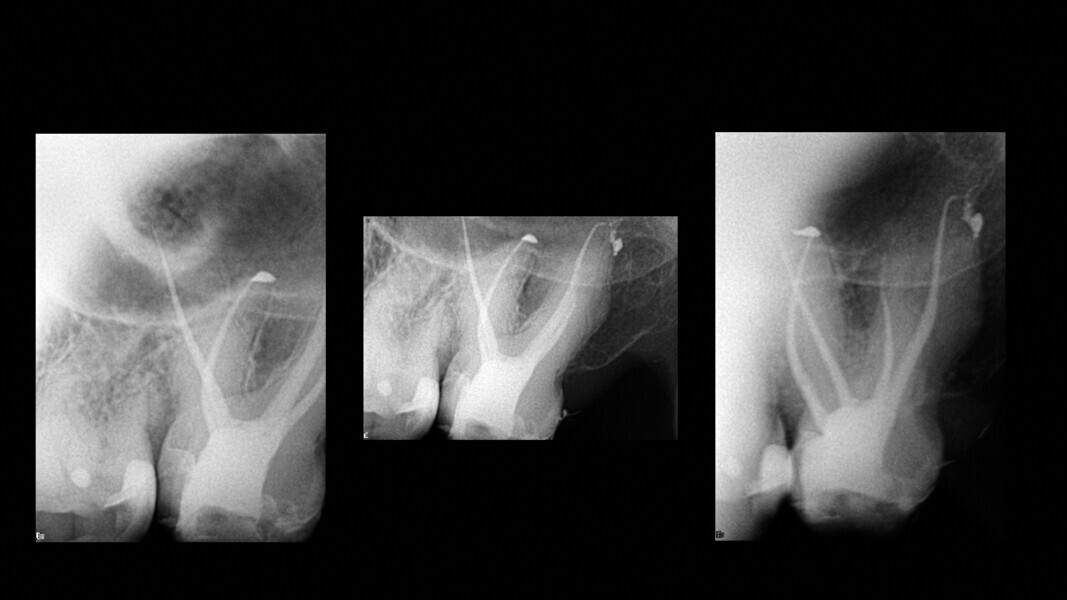

Le mode endodontique du nouveau logiciel DTX Studio Clinic permet d’ajouter de nombreuses vues et coupes transversales, ainsi que d’ajuster l’épaisseur des coupes pour vérifier le degré de calcification. Un autre avantage est la possibilité de tracer l’anatomie interne de chacune des racines et de l’ensemble du système, et de sélectionner une couleur pour chaque canal. Cette option est très utile pour examiner l’anatomie interne (Fig. 3).

Grâce à ce logiciel, il est donc possible de créer un modèle 3D de la dent et de visualiser le tracé des canaux et leurs longueurs de travail approximatives, ce qui nous donne une bonne idée de ce à quoi nous pouvons nous attendre (Fig. 4).

Dans le cas de cette deuxième molaire supérieure par exemple, la longueur de travail moyenne était d’environ 27 mm et quatre canaux étaient présents. Le type anatomique était ce que j’appelle un « double expresso », car il pose pas mal de difficultés. Ici notamment, la courbure du canal distal était très prononcée et prenait la forme d’un crochet au niveau de l’apex.